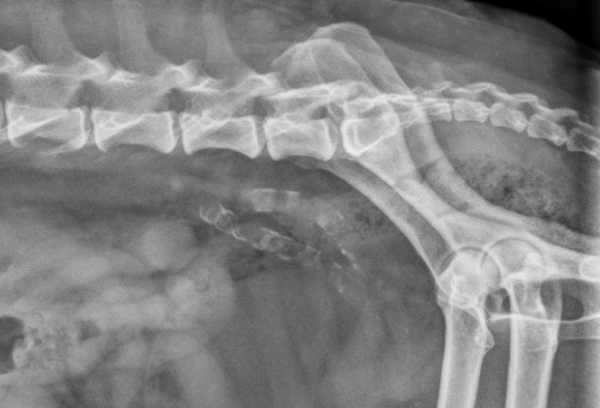

What is shown in this radiograph?

A

metastatic mineralization of the abdominal aorta and iliac arteries

11

Q

metastatic mineralization of the iliac vessels